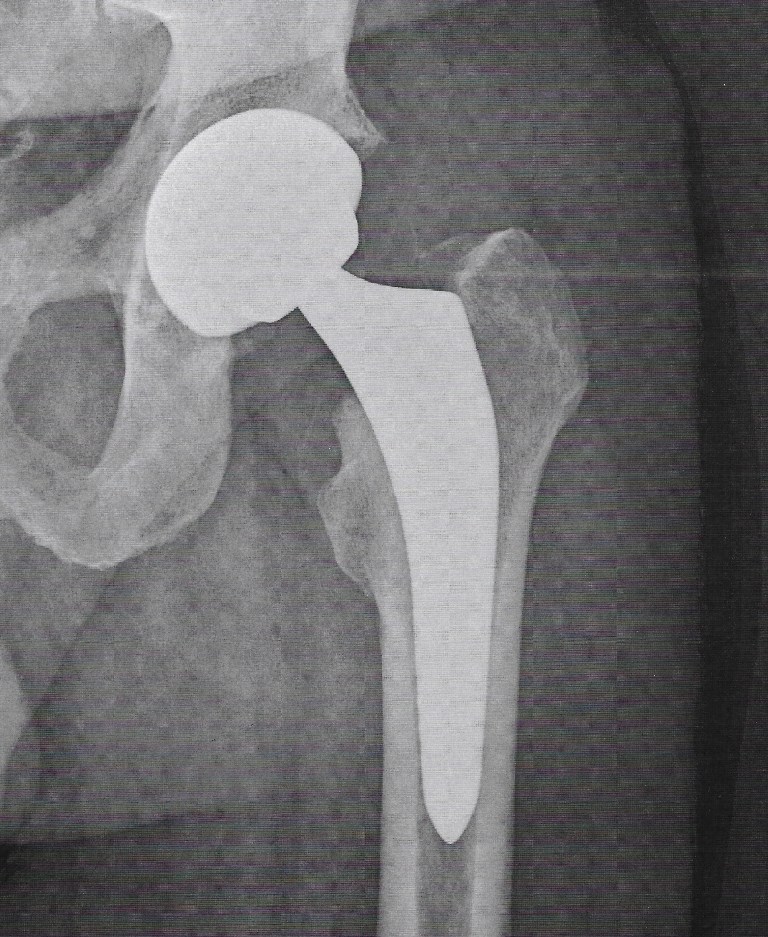

Meine Frage, ob ich meine Prothese sehen könnte, wurde aus Sterilitätsgründen verneint, aber ich habe mich recht gut vorbereitet, daher kann ich hier auch ein Referenzbild zeigen. Die eigene wäre aber trotzdem interessant gewesen.

Bei fachgerechter Operation (siehe dazu das Kapitel am Ende) beträgt die Lebensdauer der Hüft-TEP (Totalendoprothese des Hüftgelenks) heute 20 bis 25 Jahre, oft sogar länger. Offiziell werden trotzdem 15 Jahre kommuniziert, ich habe aber mit einigen Leuten gesprochen, die ihre Endoprothese ohne Probleme schon länger als 20 Jahre haben.